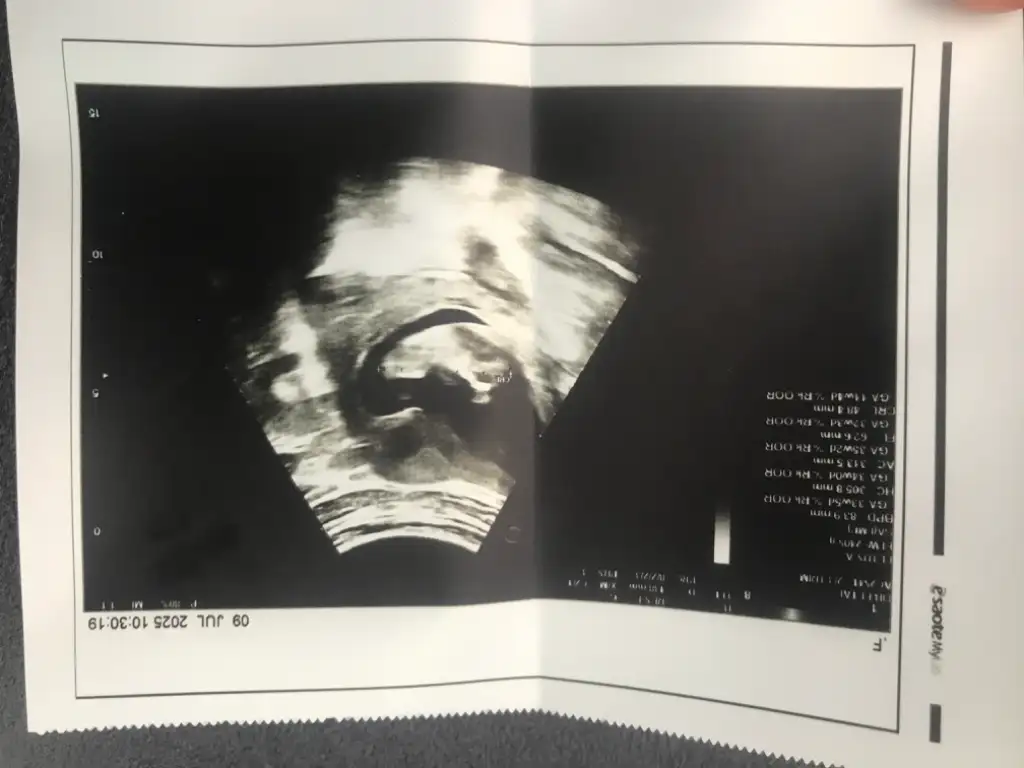

Cinsiyet tahmini yapar mısınız

Eklentiler

• IMG_8092.webp

IMG_8092.webp

22,1 KB · Görüntüleme: 8

• IMG_8091.webp

IMG_8091.webp

19,3 KB · Görüntüleme: 11